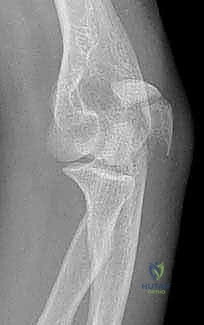

Image

TECH FIG 3 • A. A lateral radiograph illustrates a comminuted olecranon fracture with a small proximal olecranon fragment. B. An oblique view shows the fragmentation. C. A 3.5-mm limited-contact dynamic compression plate and screws contoured to wrap around the dorsal surface of the olecranon is used for fixation. (continued)